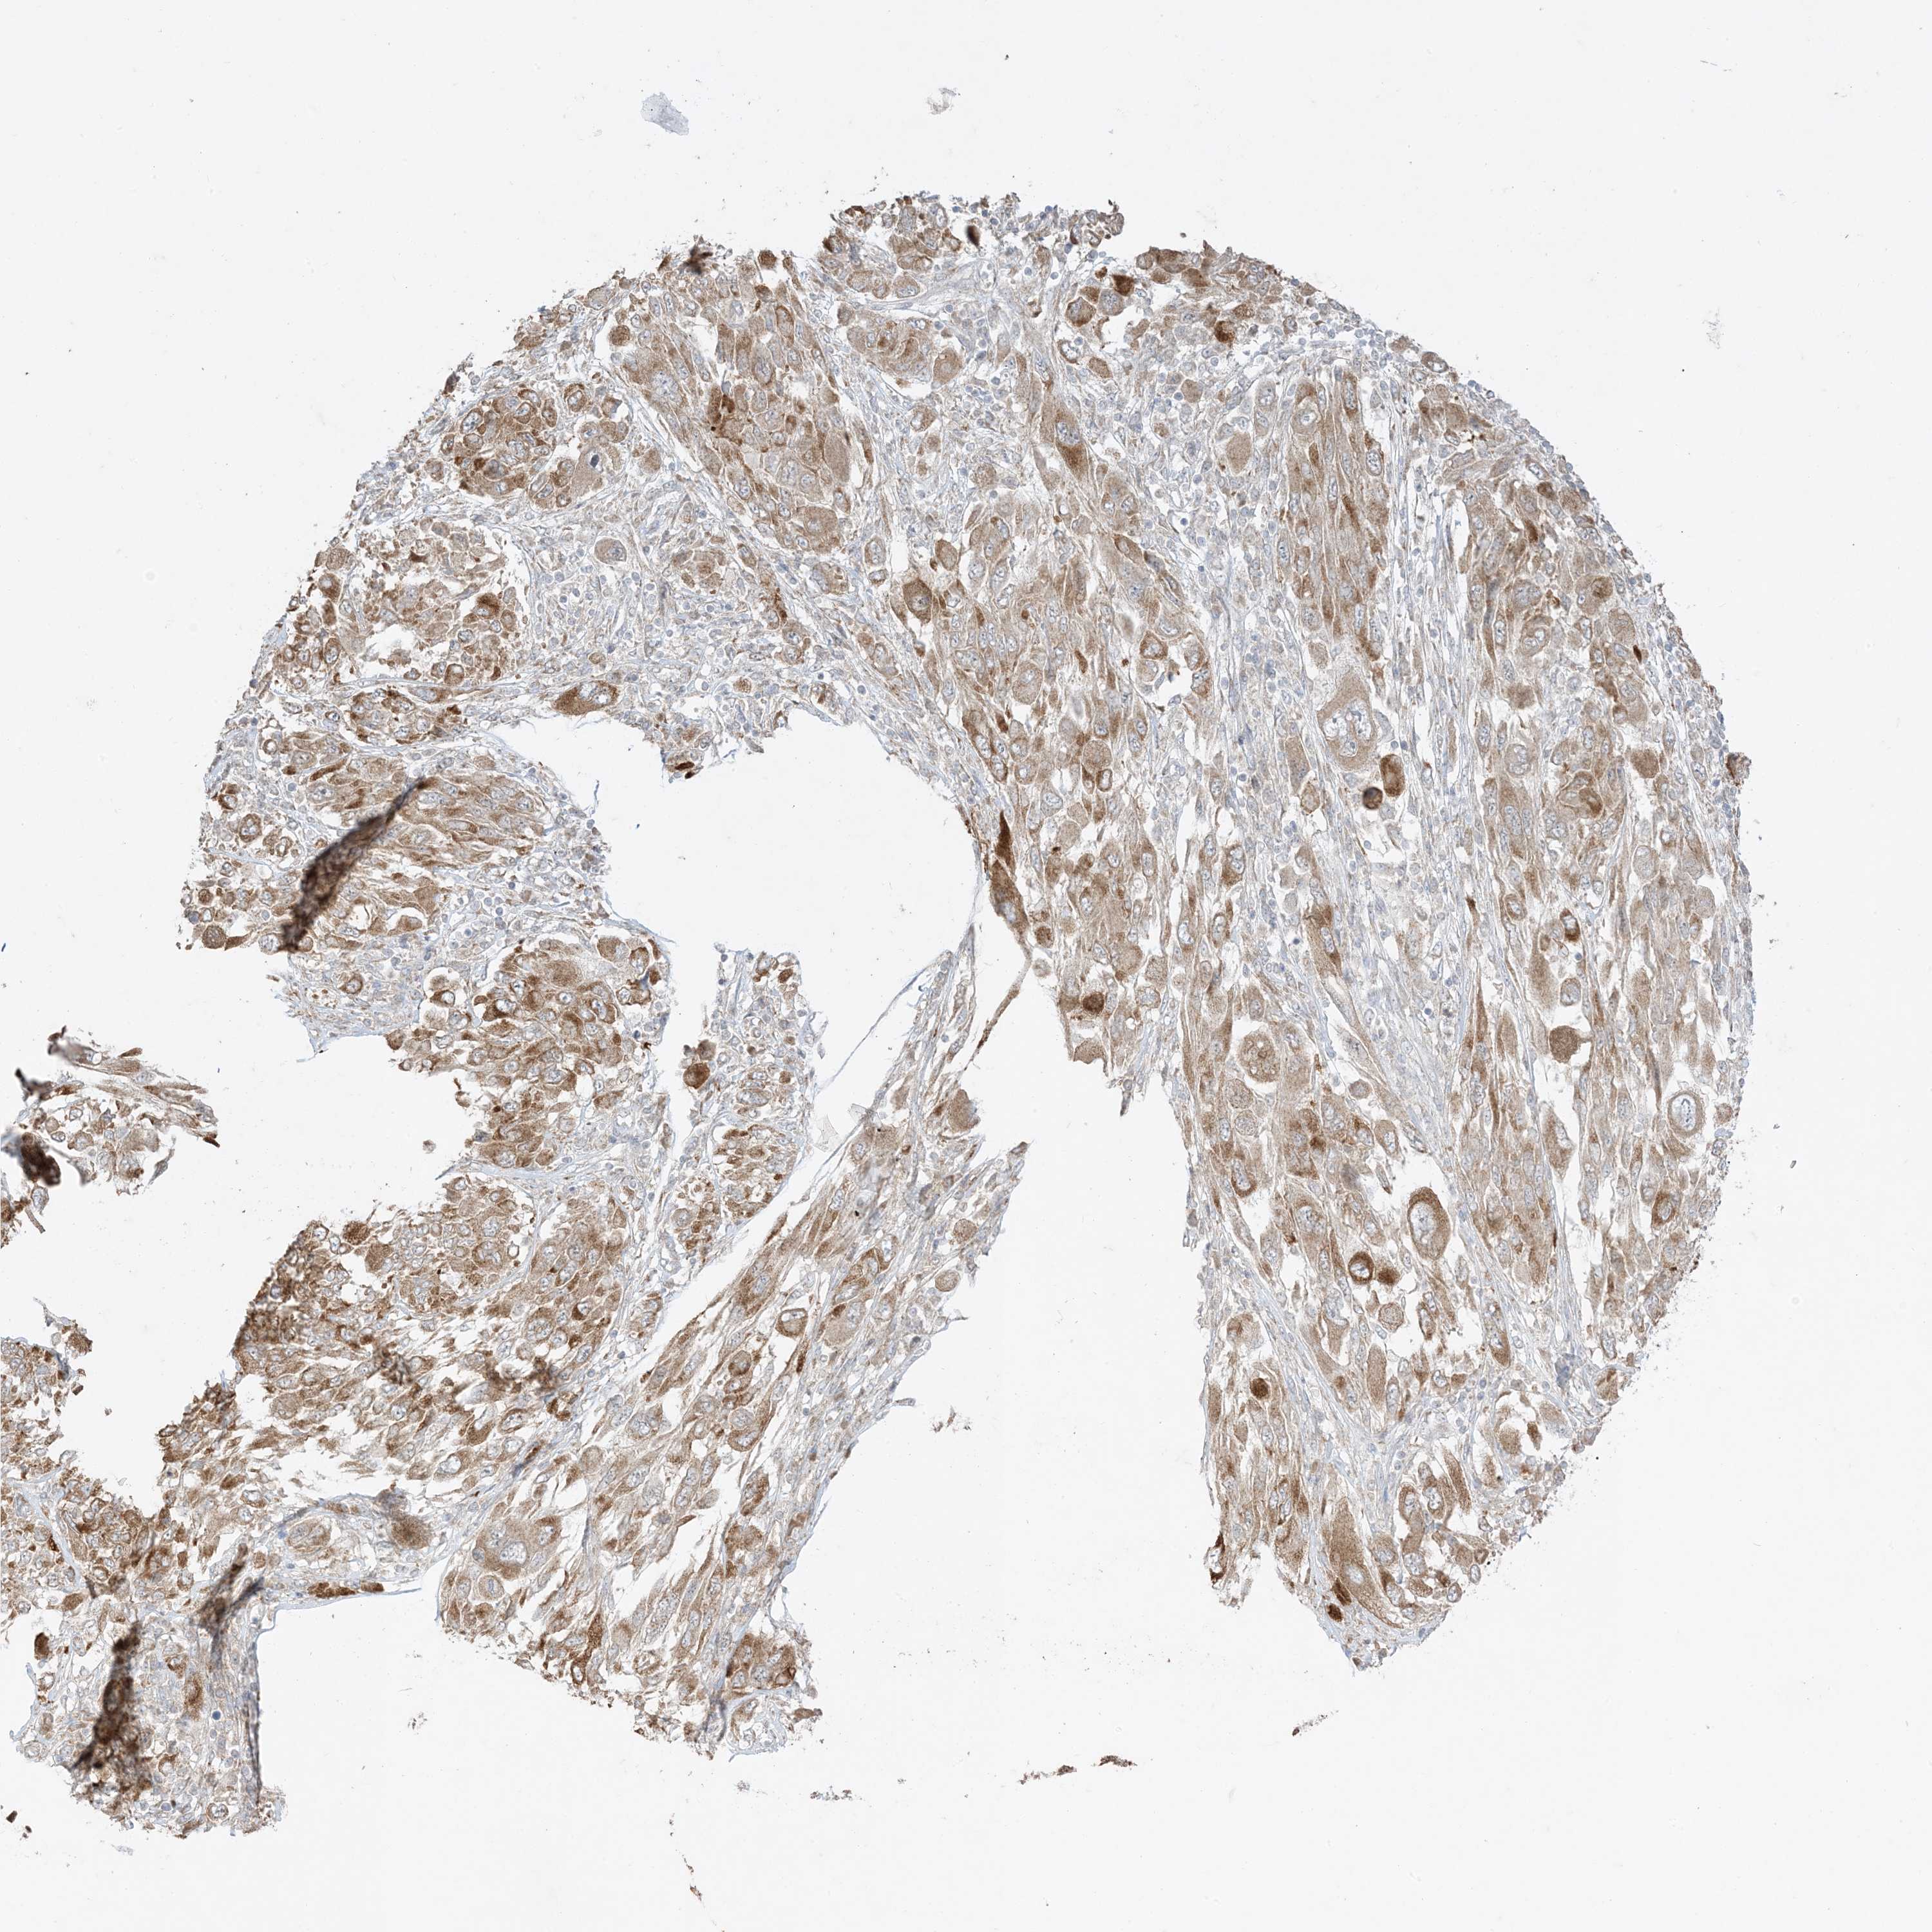

MELANOMA - Protein expressioni

A mouse-over function shows sample information and annotation data. Click on an image to view it in a full screen mode. Samples can be filtered based on level of antibody staining by selecting one or several of the following categories: high, medium, low and not detected. The assay and annotation is described here.

Note that samples used for immunohistochemistry by the Human Protein Atlas do not correspond to samples in the TCGA dataset.

Antibody stainingi

Antibody staining in the annotated cell types in the current human tissue is reported as not detected, low, medium, or high, based on conventional immunohistochemistry profiling in selected tissues. This score is based on the combination of the staining intensity and fraction of stained cells.

Each image is clickable and will lead to virtual microscopy that enables deeper exploration of all samples and also displays staining intensity scores, fraction scores and subcellular localization as well as patient and tissue information for each sample.

Antibody HPA001536

Antibody CAB035996

Staining

High

Medium

Low

Not detected

Intensity

Strong

Moderate

Weak

Negative

Quantity

>75%

75%-25%

<25%

None

Location

Nuclear

Cytoplasmic/membranous

Cytoplasmic/membranous,nuclear

Malignant melanoma, NOS

Malignant melanoma, Metastatic site